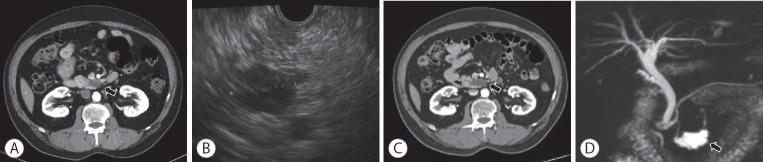

内镜超声引导下乙醇消融胰腺囊肿后坏死性胰腺炎所致十二指肠狭窄:一例报告

Duodenal Stricture due to Necrotizing Pancreatitis following Endoscopic Ultrasound-Guided Ethanol Ablation of a Pancreatic Cyst: A Case Report.

The frequency of incidental detection of pancreatic cystic lesions (PCLs) is increasing because of the frequent use of cross-sectional imaging. The appropriate treatment for PCLs is challenging, and endoscopic ultrasound-guided ablation for PCLs has been reported in several studies. Although the feasibility and efficacy of this therapeutic modality have been shown, the safety issues associated with the procedure are still a concern. We present a case of a 61-year-old man who underwent ultrasound-guided ethanol ablation for PCL and needed repeated endoscopic balloon dilatation for severe duodenal stricture caused by necrotizing pancreatitis after the cyst ablation therapy.

摘要

由于横断面成像的频繁使用,胰腺囊性病变(PCLs)的偶然检出率正在上升。PCLs的恰当治疗具有挑战性,并且在多项研究中已报道了内镜超声引导下对PCLs进行消融治疗。尽管已证明这种治疗方式的可行性和有效性,但与该操作相关的安全问题仍然令人担忧。我们报告一例61岁男性病例,该患者接受了超声引导下PCL乙醇消融治疗,在囊肿消融治疗后因坏死性胰腺炎导致严重十二指肠狭窄而需要反复进行内镜球囊扩张。